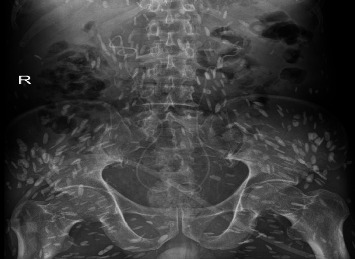

Cysticercosis refers to a disease caused by the larvae of Taenia solium parasitizing various tissues and organs of the human body. It is reported that cysticercosis is most commonly caused by the central nervous system, and retroperitoneal fibrosis is rare. We report a case of retroperitoneal fibrosis caused by cysticercosis and a urinary tract obstruction caused by retroperitoneal fibrosis, which was successfully relieved by transurethral stenting. The complex pathophysiological mechanism of cysticercosis-induced retroperitoneal fibrosis requires further study. In the diagnosis and treatment of the disease, it is very important to consider the patient's epidemiological history and the presence of parasite infection.